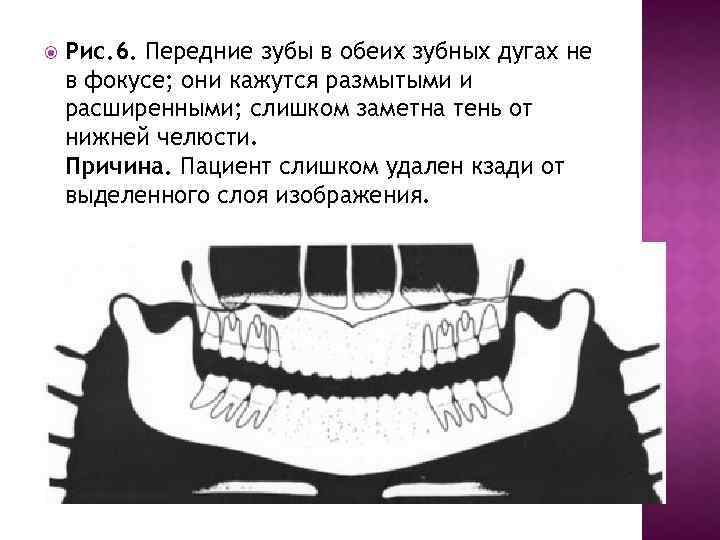

Рис. 6. Передние зубы в обеих зубных дугах не в фокусе; они кажутся размытыми и расширенными; слишком заметна тень от нижней челюсти. Причина. Пациент слишком удален кзади от выделенного слоя изображения.